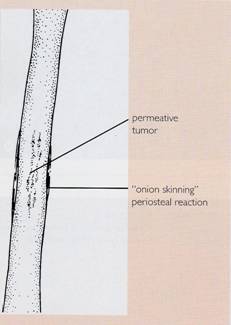

- radiografii osoase: osteoliza,

osteoscleroza sau lez mixte, reactie periostala, distructie corticala

Ewing's

sarcoma: